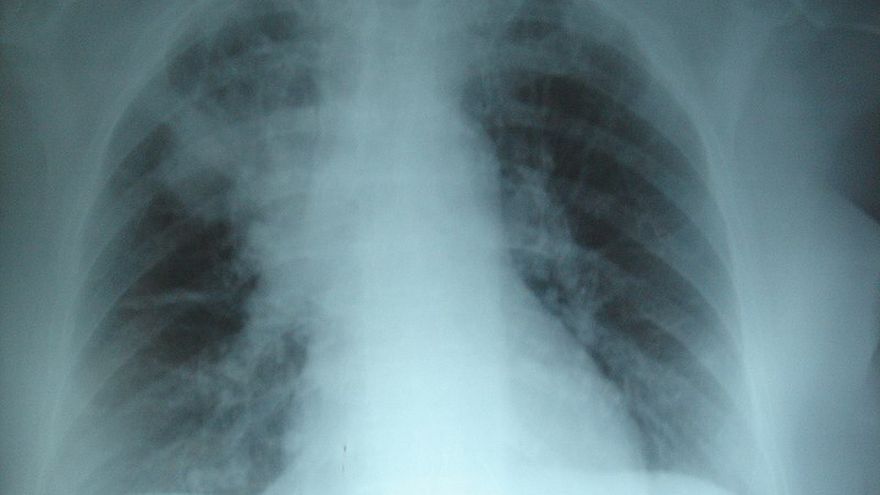

Al menos 59 casos detectados de misteriosa neumonía en China / Archivo

Las autoridades chinas informaron este domingo que 59 personas padecen una misteriosa neumonía de origen desconocido, pero descartaron que se tratara del SARS, una enfermedad viral que causó cientos de muertes en 2003.

El balance oficial es de 59 personas infectadas, a quienes se les habría detectado la enfermedad entre el 12 y el 29 de diciembre. Hay siete en estado grave y el resto, estables.

"En cuanto al agente patógeno [...] incriminado, hemos descartado varias hipótesis, sobre todo que se trate de una gripe, de una gripe aviar, de un adenovirus, del Síndrome Respiratorio Agudo Severo (SARS, por sus siglas en inglés) o del Síndrome Respiratorio de Oriente Medio (MERS)", precisó la comisión.

La epidemia actual hizo temer que se tratase del SARS, una enfermedad respiratoria altamente contagiosa que alcanzó varios países en 2003 y que dejó cerca de 800 muertos, la mayoría en territorio chino.

"Los síntomas señalados en los pacientes son comunes en varias enfermedades respiratorias y la neumonía es frecuente en periodo invernal", destacó la OMS, que matizó que la concentración de casos incita a la "prudencia".